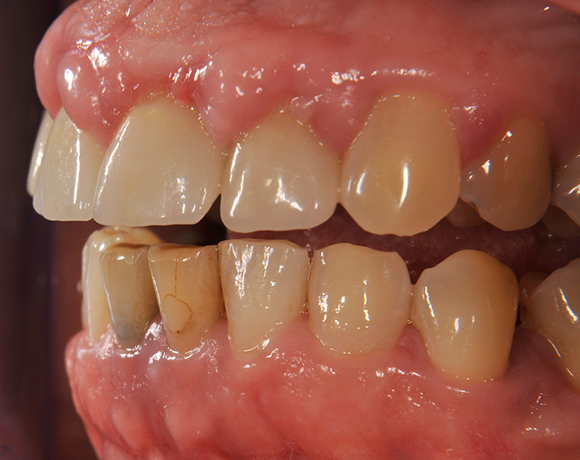

Im vorliegenden Patientenfall wurden die beiden nicht erhaltungswürdigen, mittleren Unterkieferschneidezähne durch zwei Vollkeramikimlpantate ersetzt.